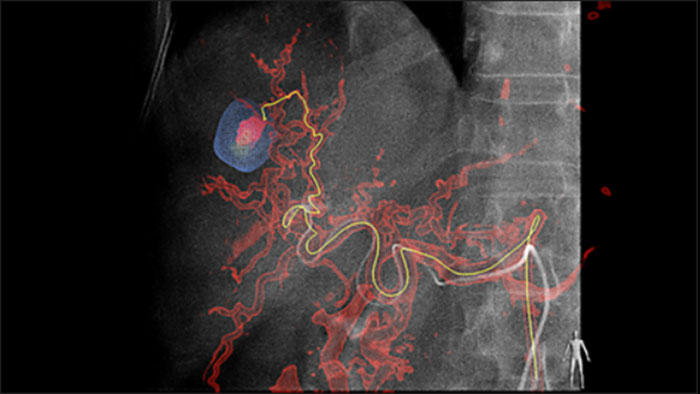

La solución de Detección automática de alimentadores puede mejorar, de forma significativa, la detección de arterias nutricias. EmboGuide le ayuda a maximizar la eficacia de sus procedimientos de quimioembolización transarterial (QET), ya que potencialmente mejora su sensibilidad, reduce los falsos positivos y maximiza la concordancia entre lectores1. EmboGuide también proporciona una guía 3D, en vivo, eficiente y basada en el flujo de trabajo con detección automática de alimentadores1.

La adopción de técnicas de quimio/radioembolización como la QET y la Radioterapia interna selectiva (Selective Internal Radiotherapy, SIRT) impulsa la necesidad de estandarización y eficiencia. Caso tras caso, debe localizar de manera confiable y uniforme los tumores, identificar todos los vasos nutricios y planificar/llevar a cabo el enfoque intervencionista apropiado. Nuestra solución de Detección automática de alimentadores puede mejorar, de manera significativa, la detección de arterias nutricias en comparación con la TC de haz cónico sola. EmboGuide le ayuda a maximizar la eficacia de sus procedimientos de QET, ya que potencialmente mejora su sensibilidad, reduce los falsos positivos y maximiza la concordancia entre lectores.1